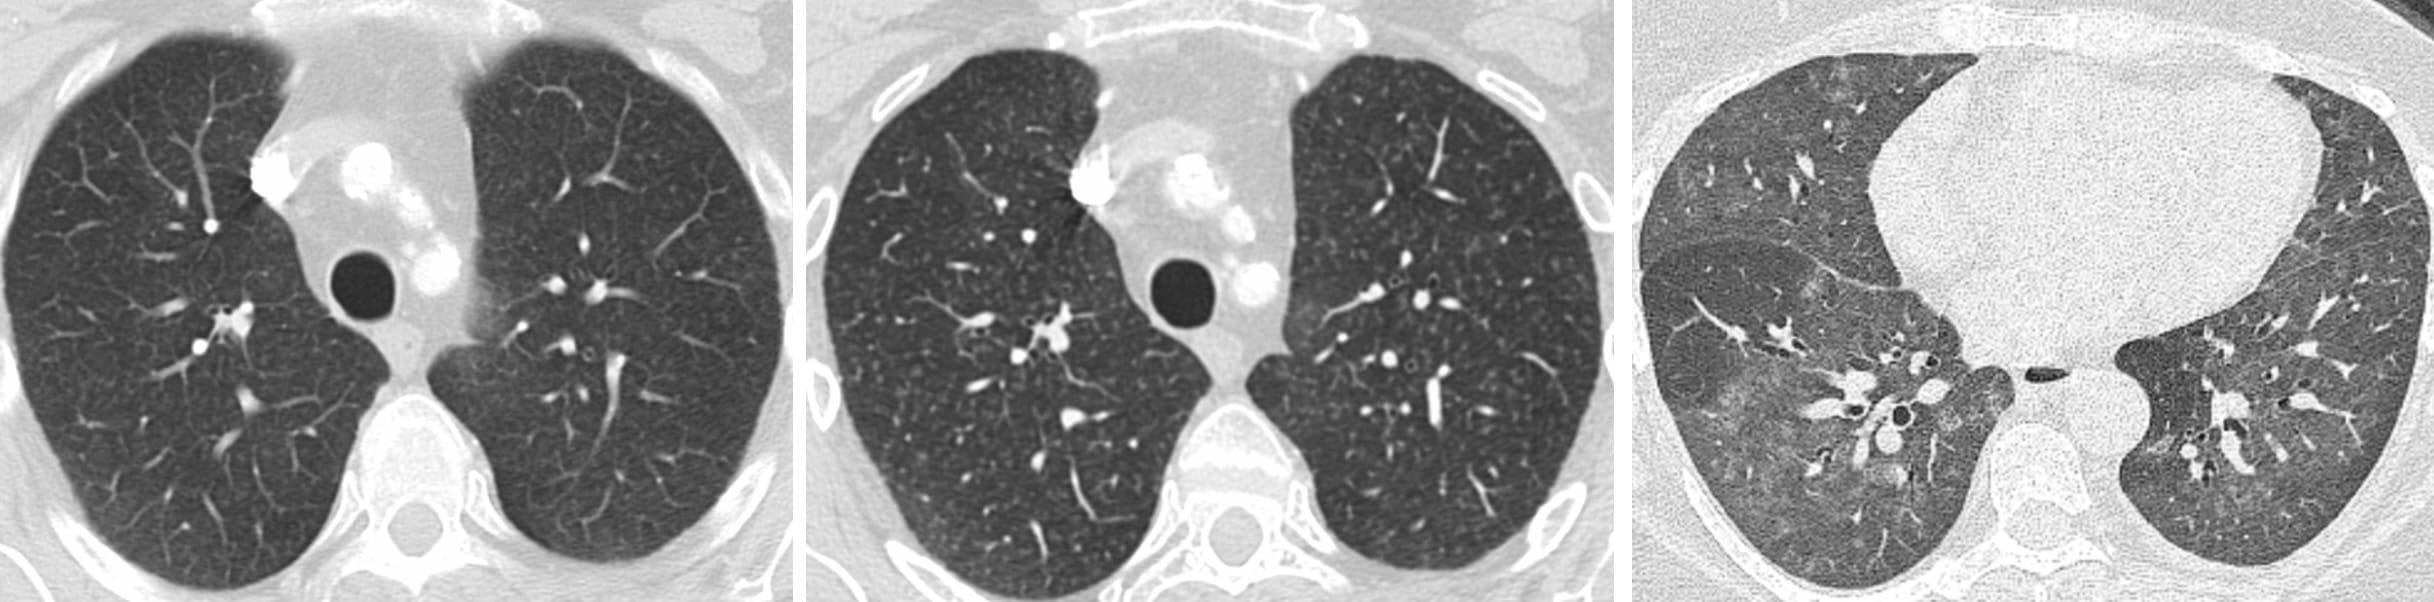

Airway-dominant phenotype

Emphysema-dominant phenotype

Mixed phenotype

We can make these distinctions on CT.

“Findings of Smoker’s Lung are present in the form of: centrilobular emphysema in the upper lungs and patchy pulmonary ground glass opacities, consistent with accumulation of Smoker’s Macrophages and, possibly, Smoking-Related Interstitial Fibrosis.”

“The cysts’ diameters in AEF are significantly larger than those in UIP and NSIP, but, at the same time, the walls are significantly thinner than those of UIP and thicker than those of centrilobular emphysema (CLE)”